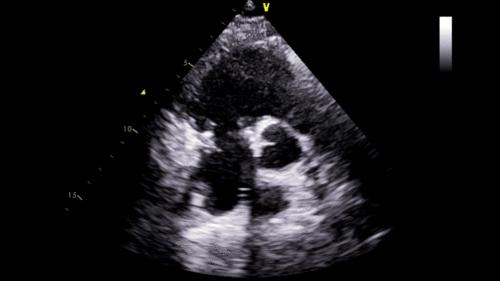

2月26日,终于等到手术的日子。由于患者是二次开胸,我院心脏中心团队格外谨慎小心,全力以赴。术中发现,患者胸部切口和胸骨都有感染,心脏周围粘连非常紧密,仅是开胸和分离心脏周围粘连就用了2个多小时。为患者建立体外循环,打开心脏探查三尖瓣时发现:三尖瓣隔叶仅为残迹,后叶缺如,前叶面积也只有正常一半,而且没有腱索和乳头肌牵拉。发生这样的病变,只有换瓣才能挽救患者的生命。可是三尖瓣瓣环已经被人工成形环固定,心内膜已经把成形环包埋起来,需要先拆掉成形环。但真是说起来容易,做起来难啊。三尖瓣瓣环比较薄,周围还有右冠状动脉和房室结。如果不小心撕坏三尖瓣瓣环,损伤冠状动脉或损伤房室结,都会造成严重并发症。吴清玉教授沉着冷静,凭着丰富的手术经验,顺利地拆除了成形环,置换好新的人工瓣膜。患者心脏复跳,手术堪称完美。由于术前准备充分,术中节血措施完备,整个手术仅使用红细胞4个单位,患者术后12天就顺利康复出院了。